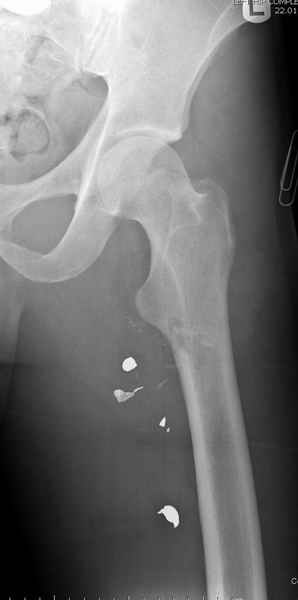

Больной с огнестрельным переломом бедра с вовлечением около 15% медиального кортекса, входное отверстие около 1 см в диаметре; стабильный, без сосудистых и неврологических признаков.

Учитывая, что больной получил травму не во время визита в церковь, и он является одним из представителем 40 миллионного “outstanding itizen”, без медицинской страховки, без работы в свои 39 лет, и без надлежающей ортопедической дисциплины у которого отсутсвует страх стрессового перелома, было рекомендовано оперативное лечение: профилактическое антеградное интрамедуллярное штифтование.

Методика штифтования при отсутствии большой зоны перелома как при онкологических профилактических штифтованиях, расверливание интрамедуллярного канала проводим с предварительным наложением дополнительного дренажного отверстия в дистальном отделе бедра (в данном случаи в канале оставили 6.5 мм канюлированный шуруп), иначе при создании давления в канале во время сверления имеется опасность эмболизации легочной артерии тромбом.